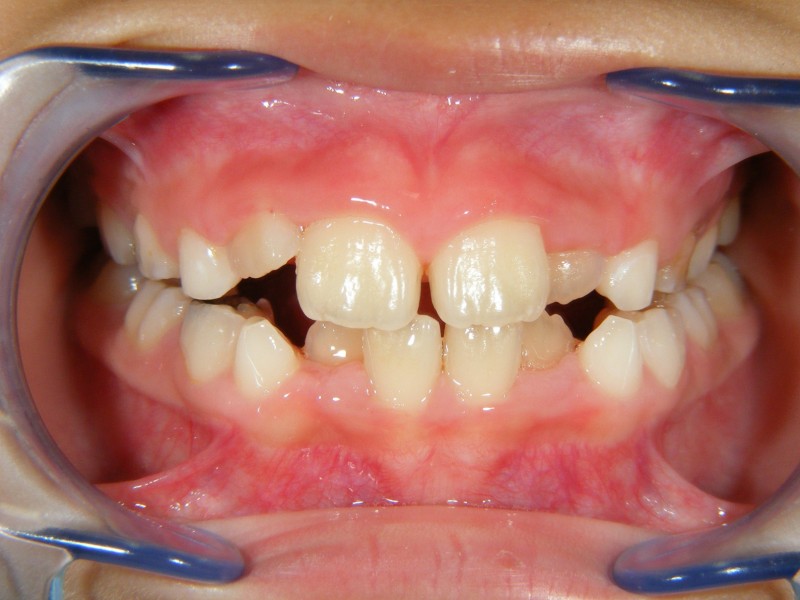

↑こちらが初診時。小学1年生。

↑こちらは、奥歯も永久歯に生え変わった6年生の写真です。

このケース、前歯の凸凹が大きかったため、何もしないで永久歯への生え変わりを待っていたら、抜歯矯正になっていた可能性もあります。

早期に治療を開始したことにより、比較的簡単に、数個の装置で歯並びを改善することが出来ました。